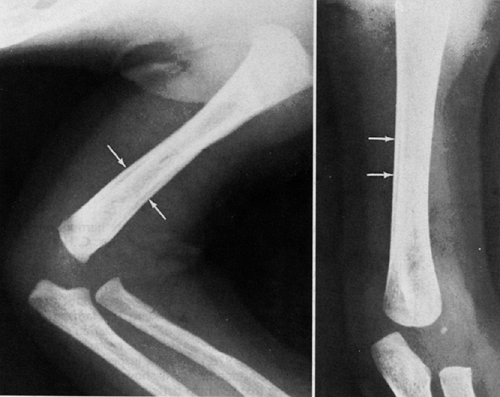

radiologist arises when the radiographic appearance of a fracture

resulting from abuse is not characteristic. Many of the fracture

patterns caused by abuse can also be seen after accidental trauma (Fig. 34.4).

In this situation, making the correct diagnosis is more difficult. In

such cases, age is one of the most important factors in differentiating

accidental from abusive trauma (31,36).

![]() |

Figure 34.4 Metaphyseal fracture of distal femur in a 13-month-old child. A: Anteroposterior view. B:

Lateral view. Was this fracture caused by abuse, or was it accidental? This fracture pattern could be seen in either situation. If the child were 4 months old, the fracture would be very suspicious for abuse. At 13 months of age, and if the child is ambulatory, it could be accidental. |